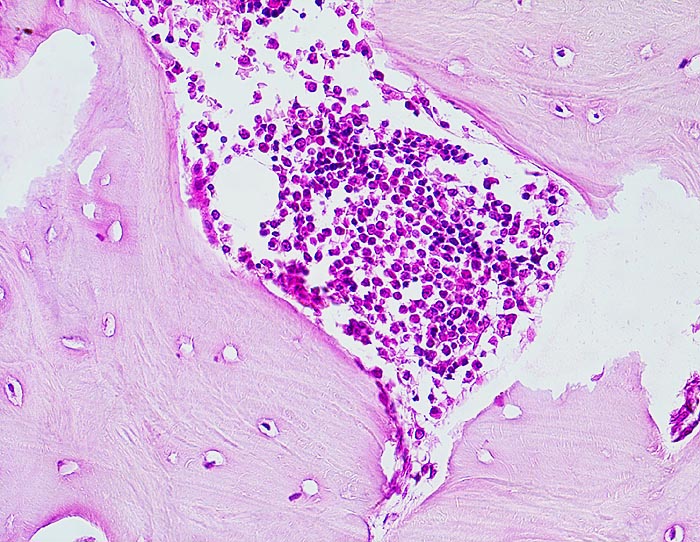

• Die Spongiosabälkchen sind auffallend verdickt, vermehrt und unregelmässig geformt.

• Riesenosteoklasten mit über 20 Kernen sind an der Knochenoberfläche erkennbar.

• Vermehrte kubische aktive Osteoblasten bauen Knochen an.

• Lockere Markfibrose.